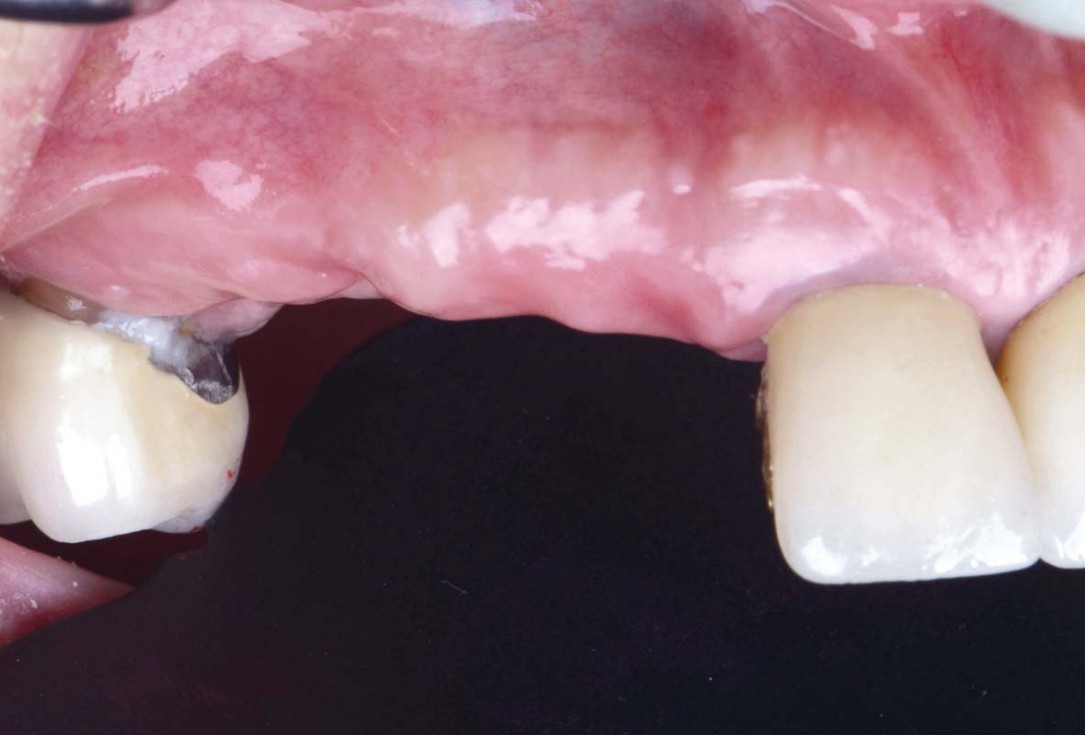

Initial clinical situation: Bone defect in the upper right maxilla (teeth #14-16)